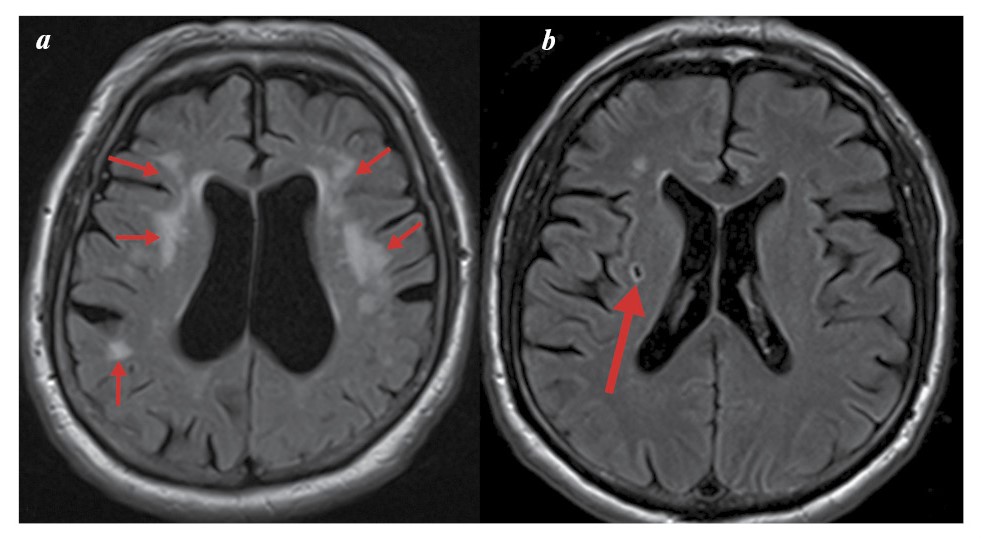

Гипоксические/ишемические процессы, возникающие в результате нарушения ЦП из-за низкого сердечного выброса и нарушения дыхания во сне, сопутствующих состояний, включая диабет и гипертонию, могут приводить к изменениям в скорлупе, мамиллярных телах, а также к локальным истончениям коры. Структурные аномалии ГМ, включая гиперинтенсивность БВ, атрофию МВД (гиппокампа), часто обнаруживают на МР-изображениях мозга как у бессимптомных, так и у пожилых людей с КН (рис. 2, 3).

Рис. 2. МР-томограммы ГМ, аксиальные проекции: а – множественные очаговые изменения (стрелки); б – ЛИ (стрелка). Собственное наблюдение.

Fig. 2. MR tomograms of the brain, axial views: a – multiple focal changes (arrows); b – lacunar infarcts (LI) (arrow). Author’s observation.